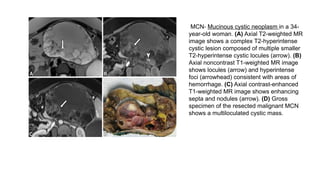

MCN- Mucinous cystic neoplasm in a 34-

year-old woman. (A) Axial T2-weighted MR

image shows a complex T2-hyperintense

cystic lesion composed of multiple smaller

T2-hyperintense cystic locules (arrow). (B)

Axial noncontrast T1-weighted MR image

shows locules (arrow) and hyperintense

foci (arrowhead) consistent with areas of

hemorrhage. (C) Axial contrast-enhanced

T1-weighted MR image shows enhancing

septa and nodules (arrow). (D) Gross

specimen of the resected malignant MCN

shows a multiloculated cystic mass.